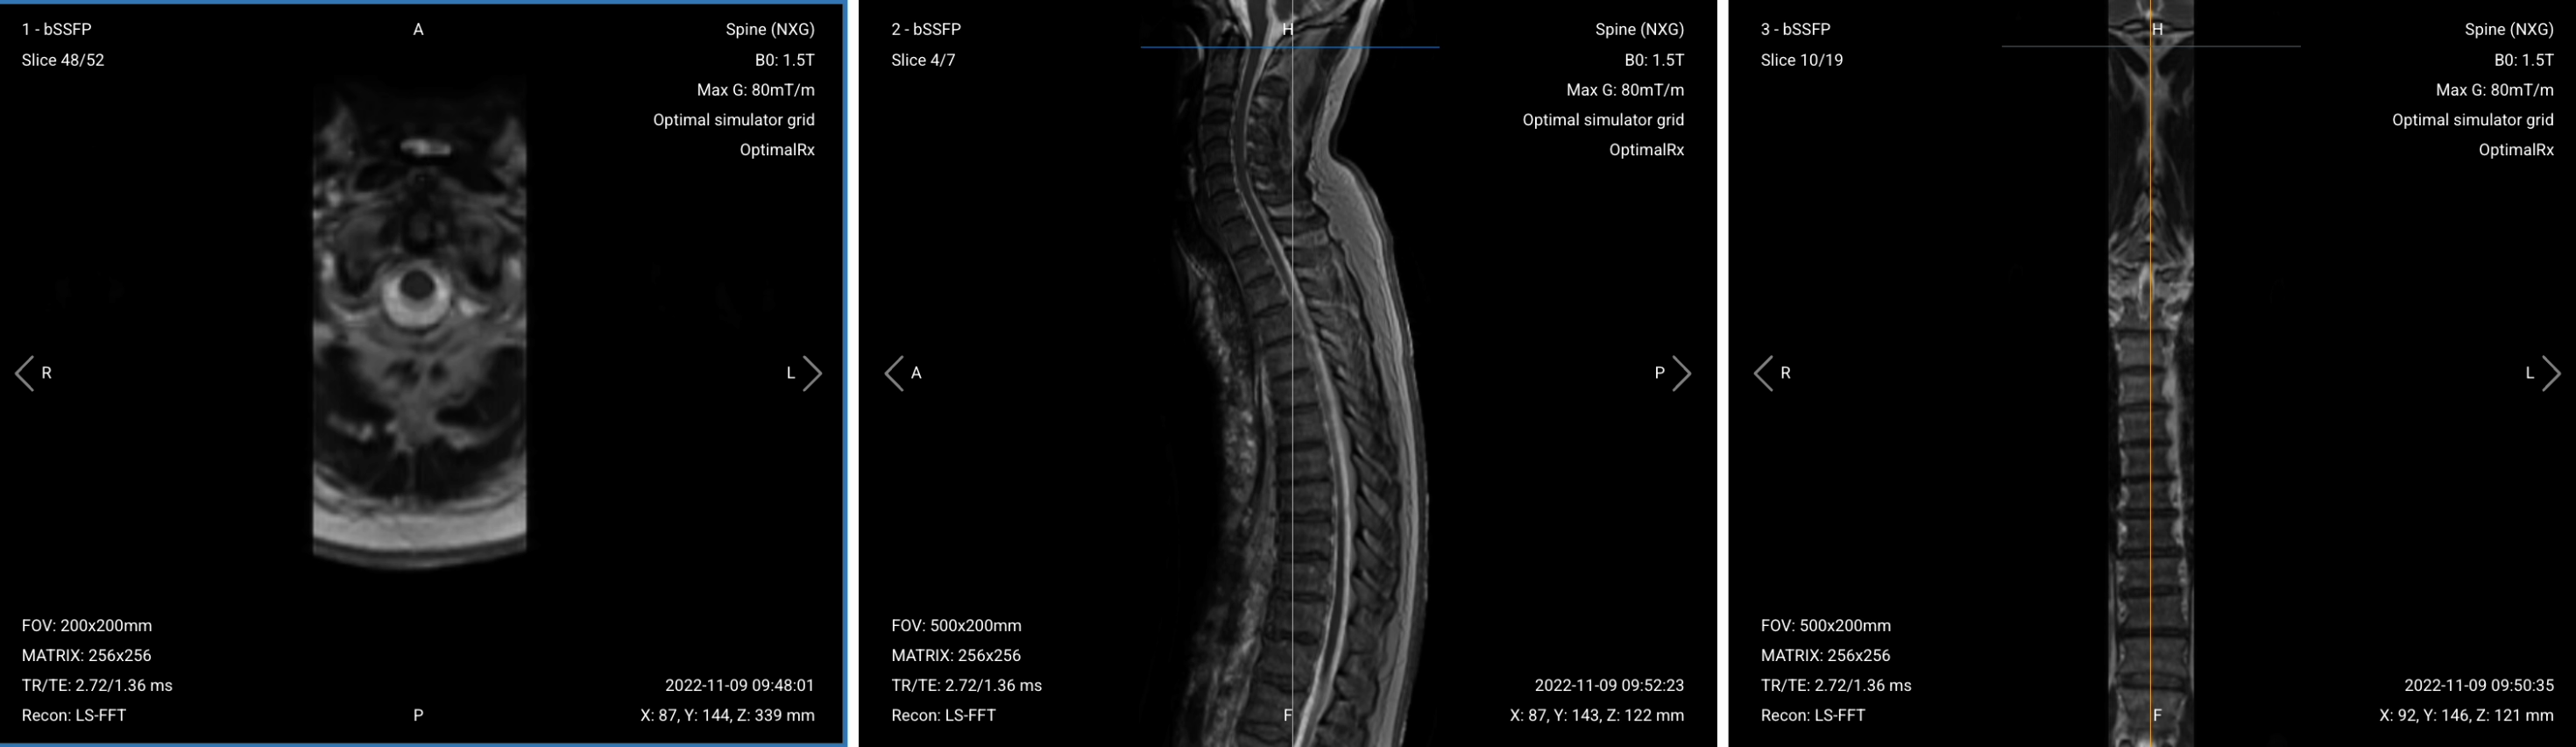

Once acquired, upload the initial localizer images into the three viewports.

Then, scroll through each of the image stacks to locate a central slice that clearly shows the anatomy of the thoracic spine.

✅ Correct Setup of Localizer Images for Thoracic Spine MRI: